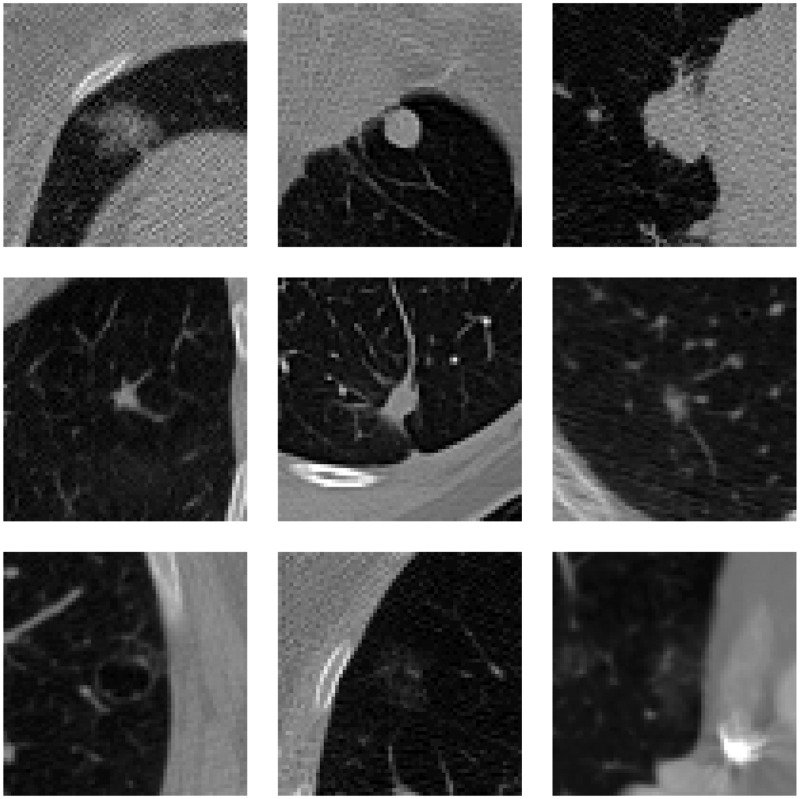

As depicted in Figure 1, pulmonary nodules can vary greatly in density, shape, size, etc. A typical pulmonary nodule exists as an isolated lesion1 in the parenchyma of the lung. Pulmonary nodules are frequently found attached to the pleural wall or vascular structures. Such juxtapleural and juxtavascular nodules, depicted in the first and second rows of Figure 1, respectively, can complicate automated nodule detection. Other nodules that can be challenging for CAD systems to detect are low-density nodules, as seen in the third row of Figure 1. Due to the variety and unique challenges, CAD systems have had difficulty achieving high performance for all varieties

Figure 1.

Different types of pulmonary nodules: juxtapleural (top row), juxtavascular (middle row), and low-density (bottom row).